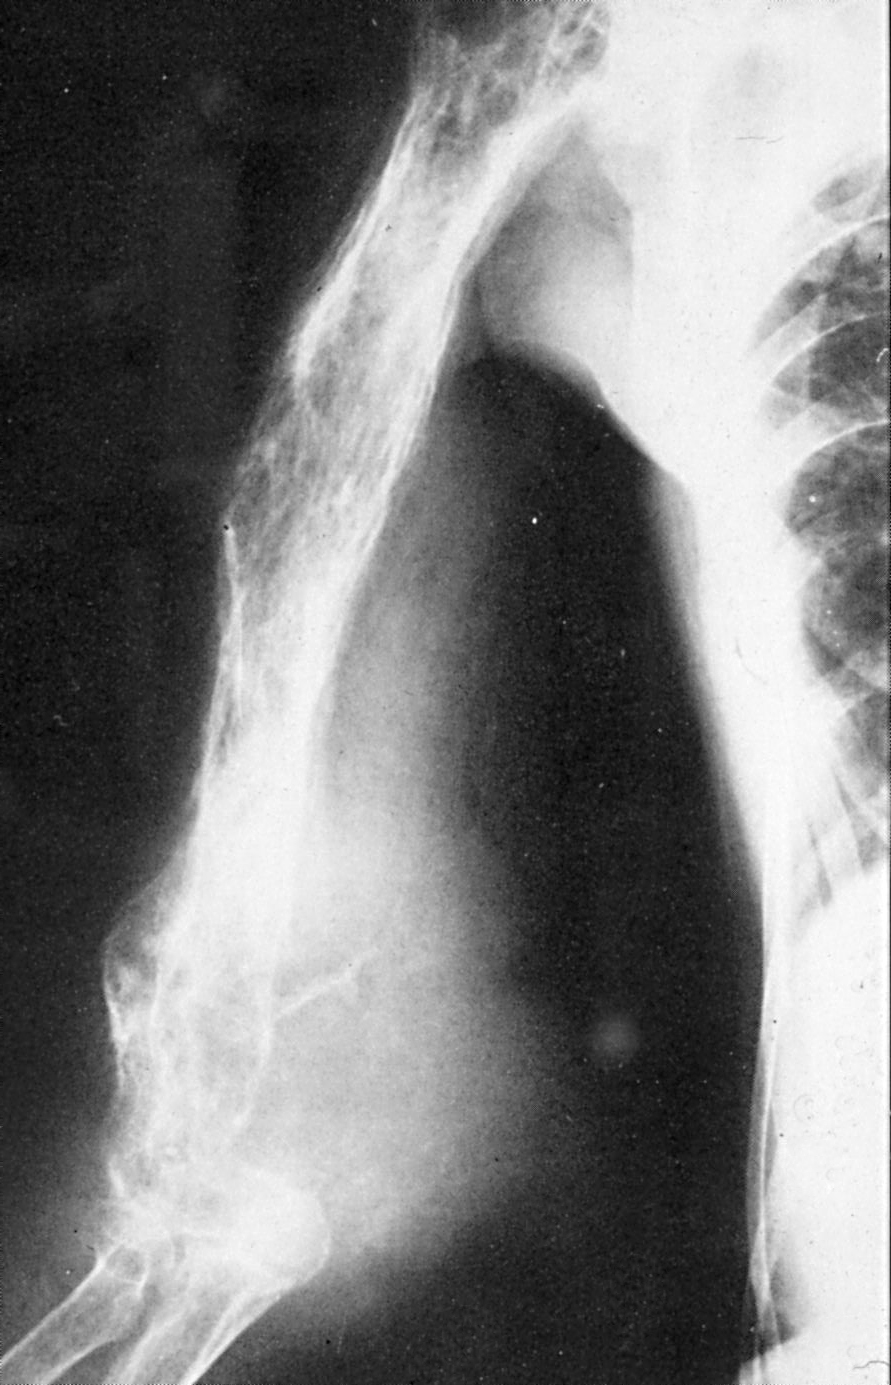

transformation to of Paget disease of the... Download Scientific Diagram Paget's Disease And Osteosarcoma It is presumed benign in nature. It occurs at increased rates in individuals with paget disease of bone, after. Sarcomatous transformation is most often seen in severe,. Pagetoid osteosarcoma is a complication of paget’s disease of bone. Osteosarcoma arising in paget’s disease patients have been found to have a higher incidence of p53 mutation, as well as mutations to other. Paget's Disease And Osteosarcoma.